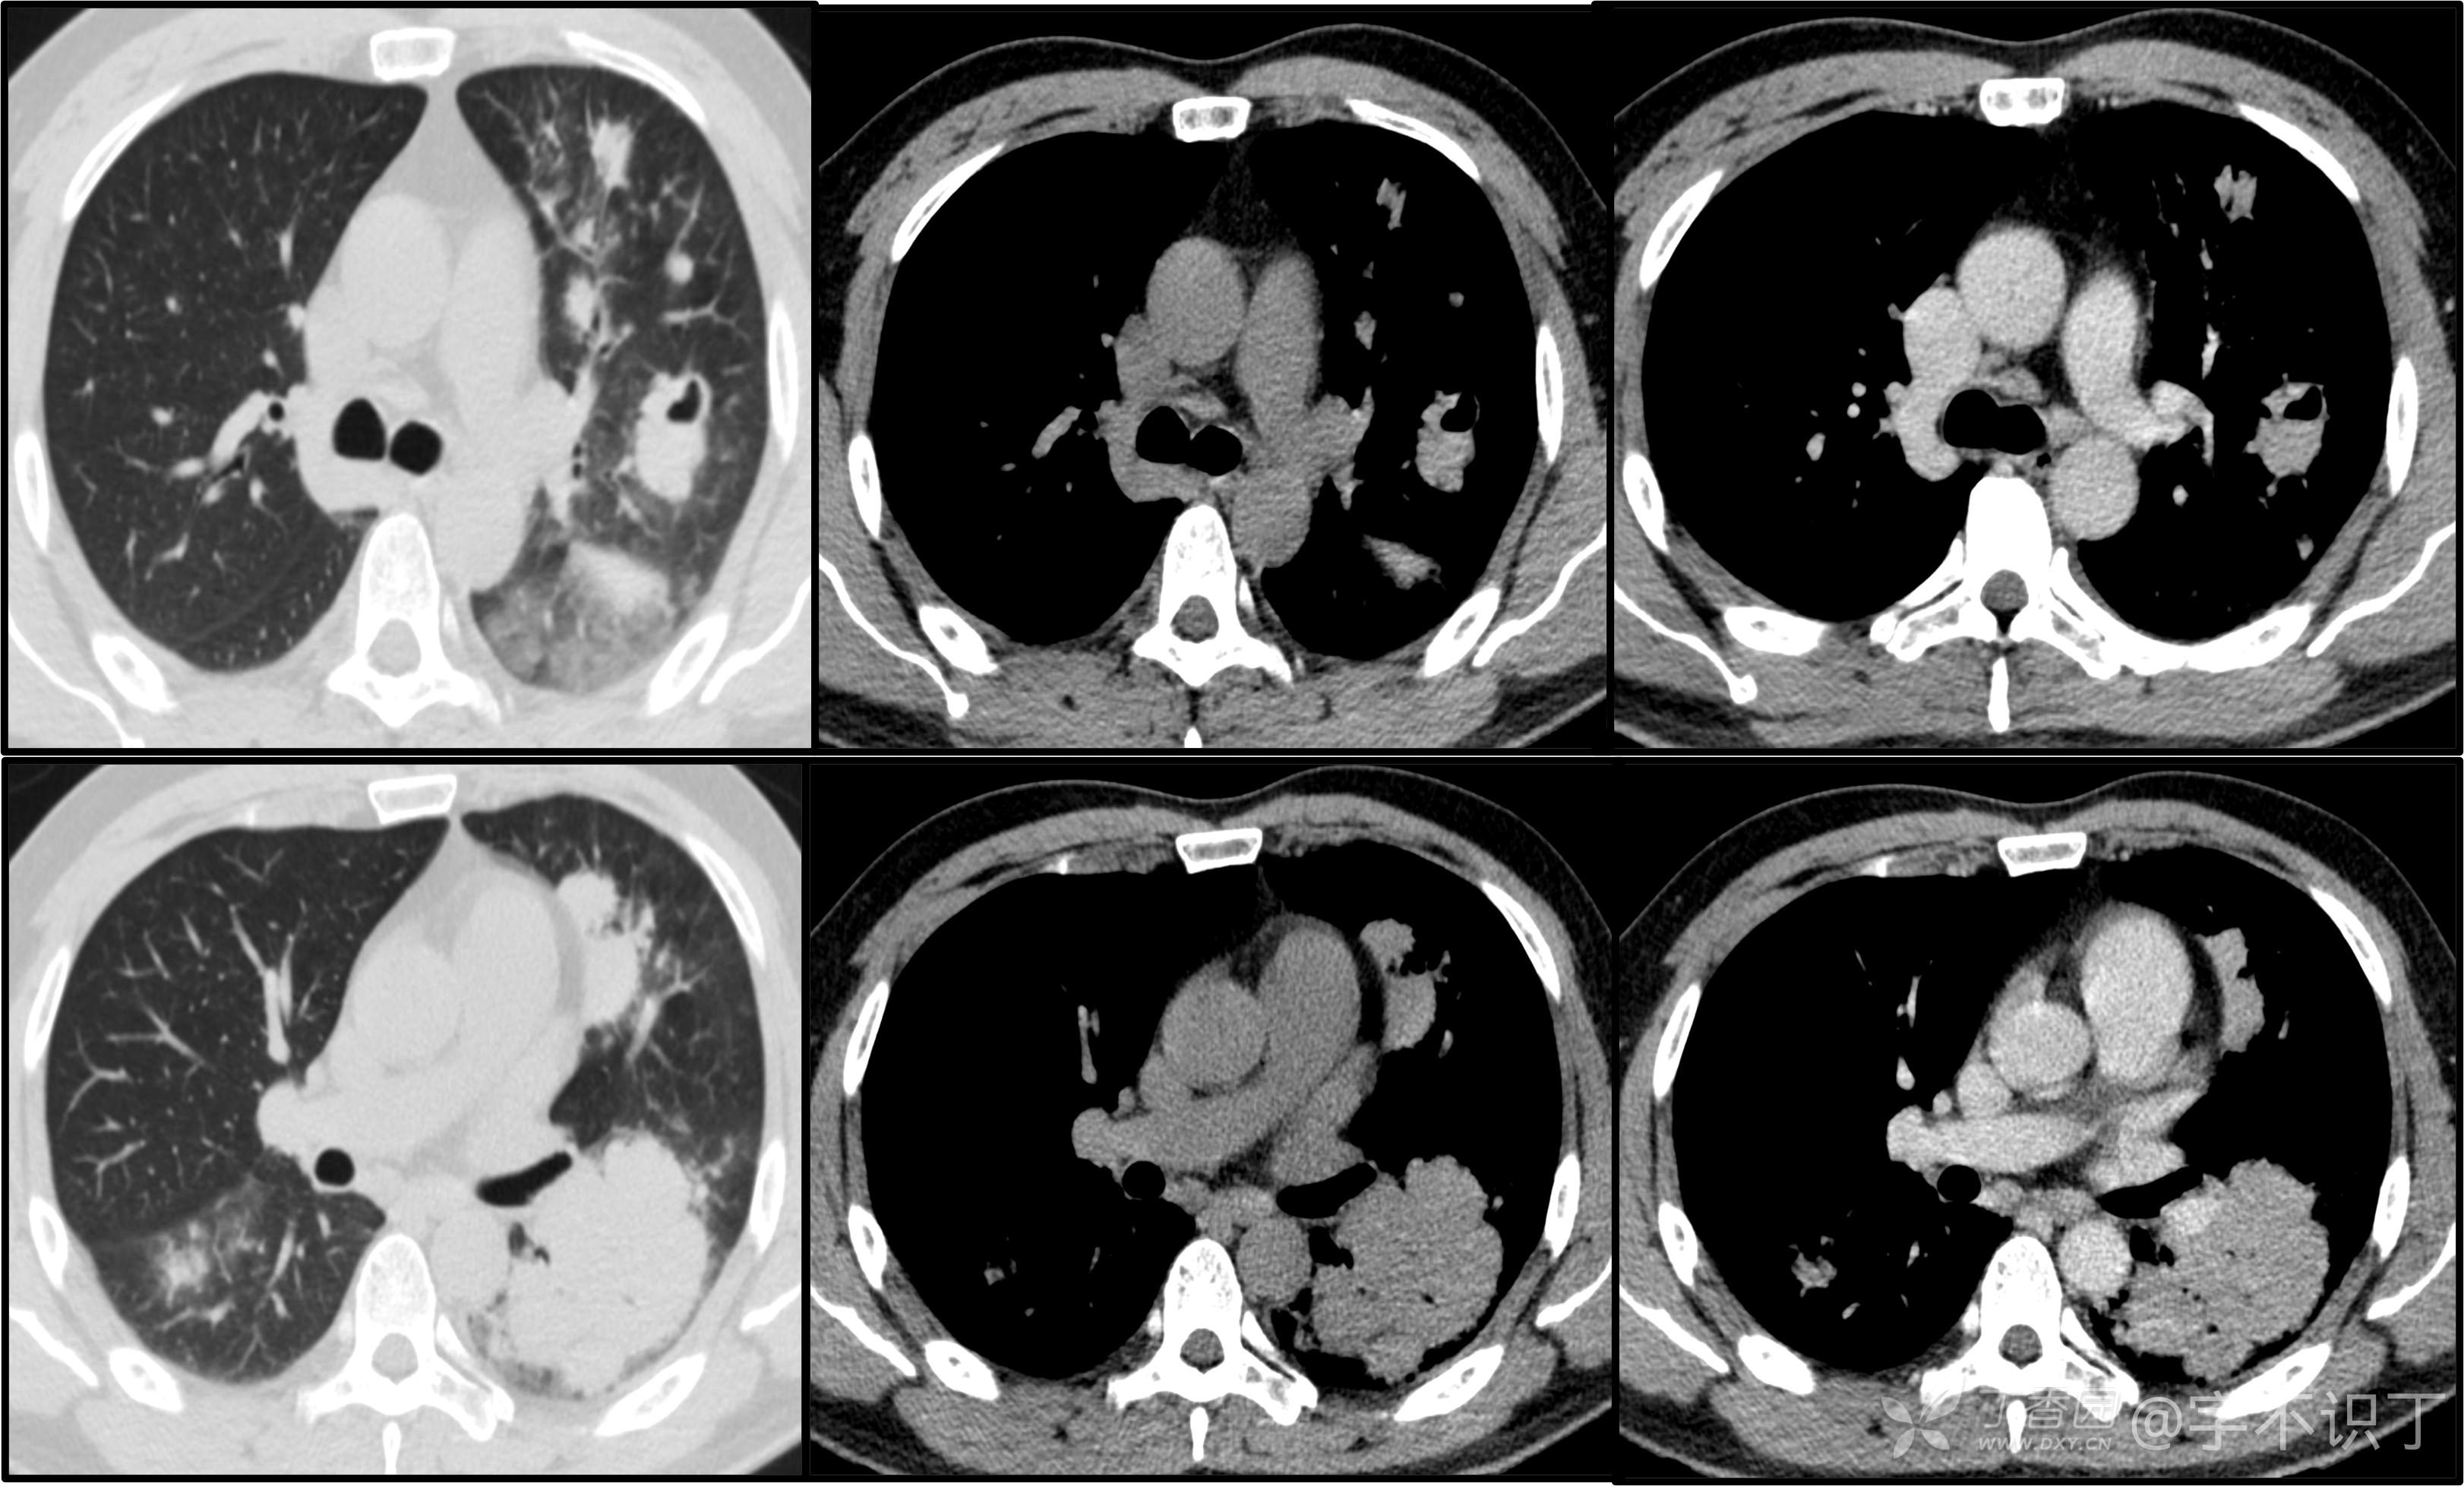

胸部病例讨论

患者性别:男

患者年龄:40岁

主诉:反复咳嗽2年,再发2月,咯血发热5天

简要病史:2年前无明显诱因出现阵发性干咳;2月前咳嗽症状较前加重,有少量白色粘液样痰,未经特殊处理,7天前咳嗽症状较前加重,伴咳黄脓样痰,痰中带血丝,予以哌拉西林舒巴坦+莫西沙星抗感染及祛痰等对症支持治疗,未觉好转,予以拉氧头孢、左氧氟沙星、布洛芬、氨溴索等对症处理,咳嗽、咳痰症状未缓解,仍有发热

体格检查:曾从事装修等工作,近半年从事煤矿管理工作。近期饮酒较频繁。既往有冶游史。

辅助检查:血液病原菌培养、分枝杆菌涂片检查、真菌涂片检查、一般细菌涂片检查、痰培养均阴性